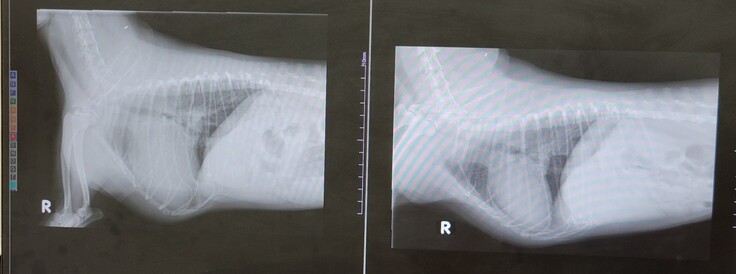

左が昨日の状態です。心臓も大きく、靄がかかっております。

昨日、23日の手術前の検査ということで、午前中に病院へいったところ、残念ながら肺水腫が再発しており、もう手術は待ったなし、という状況となりました。

肺水腫はあるものの、その他術前検査の結果自体は良好であったため、23日に正式に手術確定、ということで、あとはそこへ向かうのみ・・・だったのですが、今朝方にかけて、容体が悪化しました。

自宅の酸素室も、なかなか居座らないので、朝イチに病院へ連れて行ったところ、肺水腫が悪化しておりました。

ぷらむは肺水腫3回目となり、繰り返すごとに肺の機能が低下するので、治りも悪くなります。